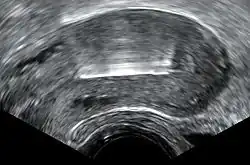

Inmediatamente antes de la inserción, el clínico realizará un examen pélvico para determinar la posición del útero.[23] Tras el examen pélvico, se mantiene abierta la vagina con un espéculo.[39] Se utiliza un tenáculo para estabilizar el cuello uterino y el útero.[39] Se puede utilizar un sonda uterina para medir la longitud y la dirección del canal cervical y el útero con el fin de disminuir el riesgo de perforación uterina. El diu se coloca utilizando un tubo estrecho, que se introduce a través del cuello uterino hasta el útero. Unos hilos cortos de monofilamento de plástico/nylon cuelgan del útero hacia la vagina. El clínico recortará los hilos para que sólo sobresalgan 3 o 4 cm del cuello uterino y permanezcan en la parte superior de la vagina. Los hilos permiten a la paciente o al clínico comprobar periódicamente que el diu sigue en su sitio y facilitan la extracción del dispositivo.[23]